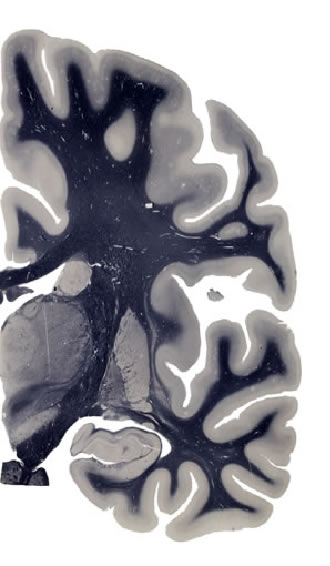

Hi-Resolution Sections · Cells (Nissl Staining) · Virtual Microscopy

Frontal sections (Nissl) from the Atlas Brain:

Slice ID:

r3-0720

Plate NR:

ca 35-36

Position:

17,9 mm